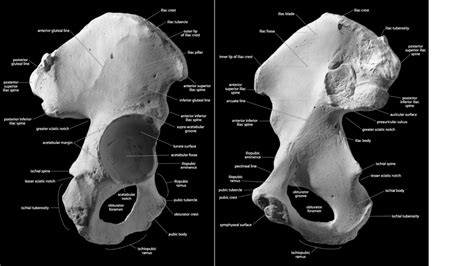

The os coxae is a large, irregular bone that forms the sides of the pelvis. As mentioned earlier, it’s actually composed of three bones: the ilium, ischium, and pubis. These bones are separate in childhood but fuse together during adolescence to form a single, solid structure. The point where these three bones meet is called the acetabulum, which is the socket for the head of the femur (thigh bone), forming the hip joint. Each of these components has unique features and landmarks that are essential to understand.

The ilium is the largest and most superior of the three bones. It forms the upper part of the hip bone and is characterized by its large, fan-shaped ala or wing. The iliac crest, the superior border of the ilium, is a prominent ridge that can be felt through the skin. This crest serves as an attachment site for abdominal muscles and is an important landmark for medical procedures. The anterior superior iliac spine (ASIS) and posterior superior iliac spine (PSIS) are palpable bony projections at the anterior and posterior ends of the iliac crest, respectively. These spines are used as reference points in physical examinations and for measuring pelvic alignment. The iliac fossa is a large, concave surface on the internal aspect of the ilium, providing attachment for the iliacus muscle. The greater sciatic notch, located on the posterior border of the ilium, is a large notch that is converted into a foramen (opening) by ligaments, allowing passage for the sciatic nerve and other structures.

The ischium forms the posteroinferior part of the os coxae. It is characterized by the ischial tuberosity , a large, rounded prominence that we sit on! When you’re sitting down, you’re primarily supported by your ischial tuberosities. The ischial spine projects medially from the posterior border of the ischium, separating the greater and lesser sciatic notches. The lesser sciatic notch is located inferior to the ischial spine and is smaller than the greater sciatic notch. The ramus of the ischium is a bony extension that joins with the inferior pubic ramus to form the ischiopubic ramus. This bony complex contributes to the inferior border of the obturator foramen, a large opening in the hip bone.

The pubis forms the anterior and inferior part of the os coxae. It consists of a body, a superior pubic ramus, and an inferior pubic ramus. The pubic symphysis is a cartilaginous joint where the bodies of the two pubic bones meet in the midline. This joint allows for slight movement, which is important during childbirth. The superior pubic ramus extends laterally from the body of the pubis and contributes to the acetabulum. The inferior pubic ramus extends inferiorly and joins with the ischial ramus to form the ischiopubic ramus. The pubic crest is a ridge on the superior border of the body of the pubis, serving as an attachment site for abdominal muscles. The obturator foramen is a large opening bounded by the pubis and ischium. Though large, it’s mostly covered by the obturator membrane, but it still allows passage for nerves and blood vessels.